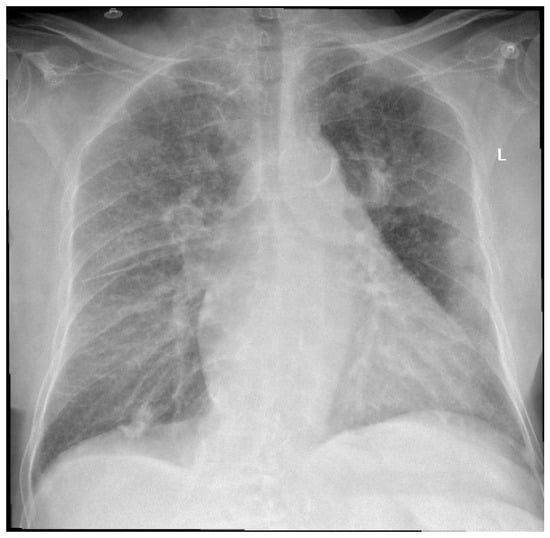

An 83-year-old female patient was admitted to the Orthopedics—Traumatology Department with a left femoral neck fracture (FNF) garden type IV due to a fall from the same height. Upon preoperative examination, the following associated comorbidities were diagnosed: bronchopneumonia (Figure 1), chronic ischemic heart disease (IHD), high blood pressure (HBP) stage 2, left ventricular failure NYHA (New York Heart Association) type 2 with a left ventricle ejection fraction (LVEF) of 50%, moderate aortic valve stenosis (mean gradient 34 mmHg, aortic valve area 10 mm), tricuspid regurgitation grade 2, and permanent atrial fibrillation (AFib), for which she was taking oral anticoagulants (rivaroxaban, 20 mg, Xarelto®, Leverkusen, Germany), diuretics (spironolactone/furosemide 50 mg/20 mg, Diurex®, Niles, IL, USA), and beta-blockers (nebivolol, 5 mg, Nebilet®, New York, NY, USA).

Figure 1.

Chest X-ray at admission—describing small left pleural effusion; bilateral diffuse reticule-micronodular interstitial lung pattern; questionable opacities at the level of the posterior left VI costal arch and right intercostal XI space; pulmonary vascular congestion; global enlarged heart; atherosclerotic aorta. L—left side.